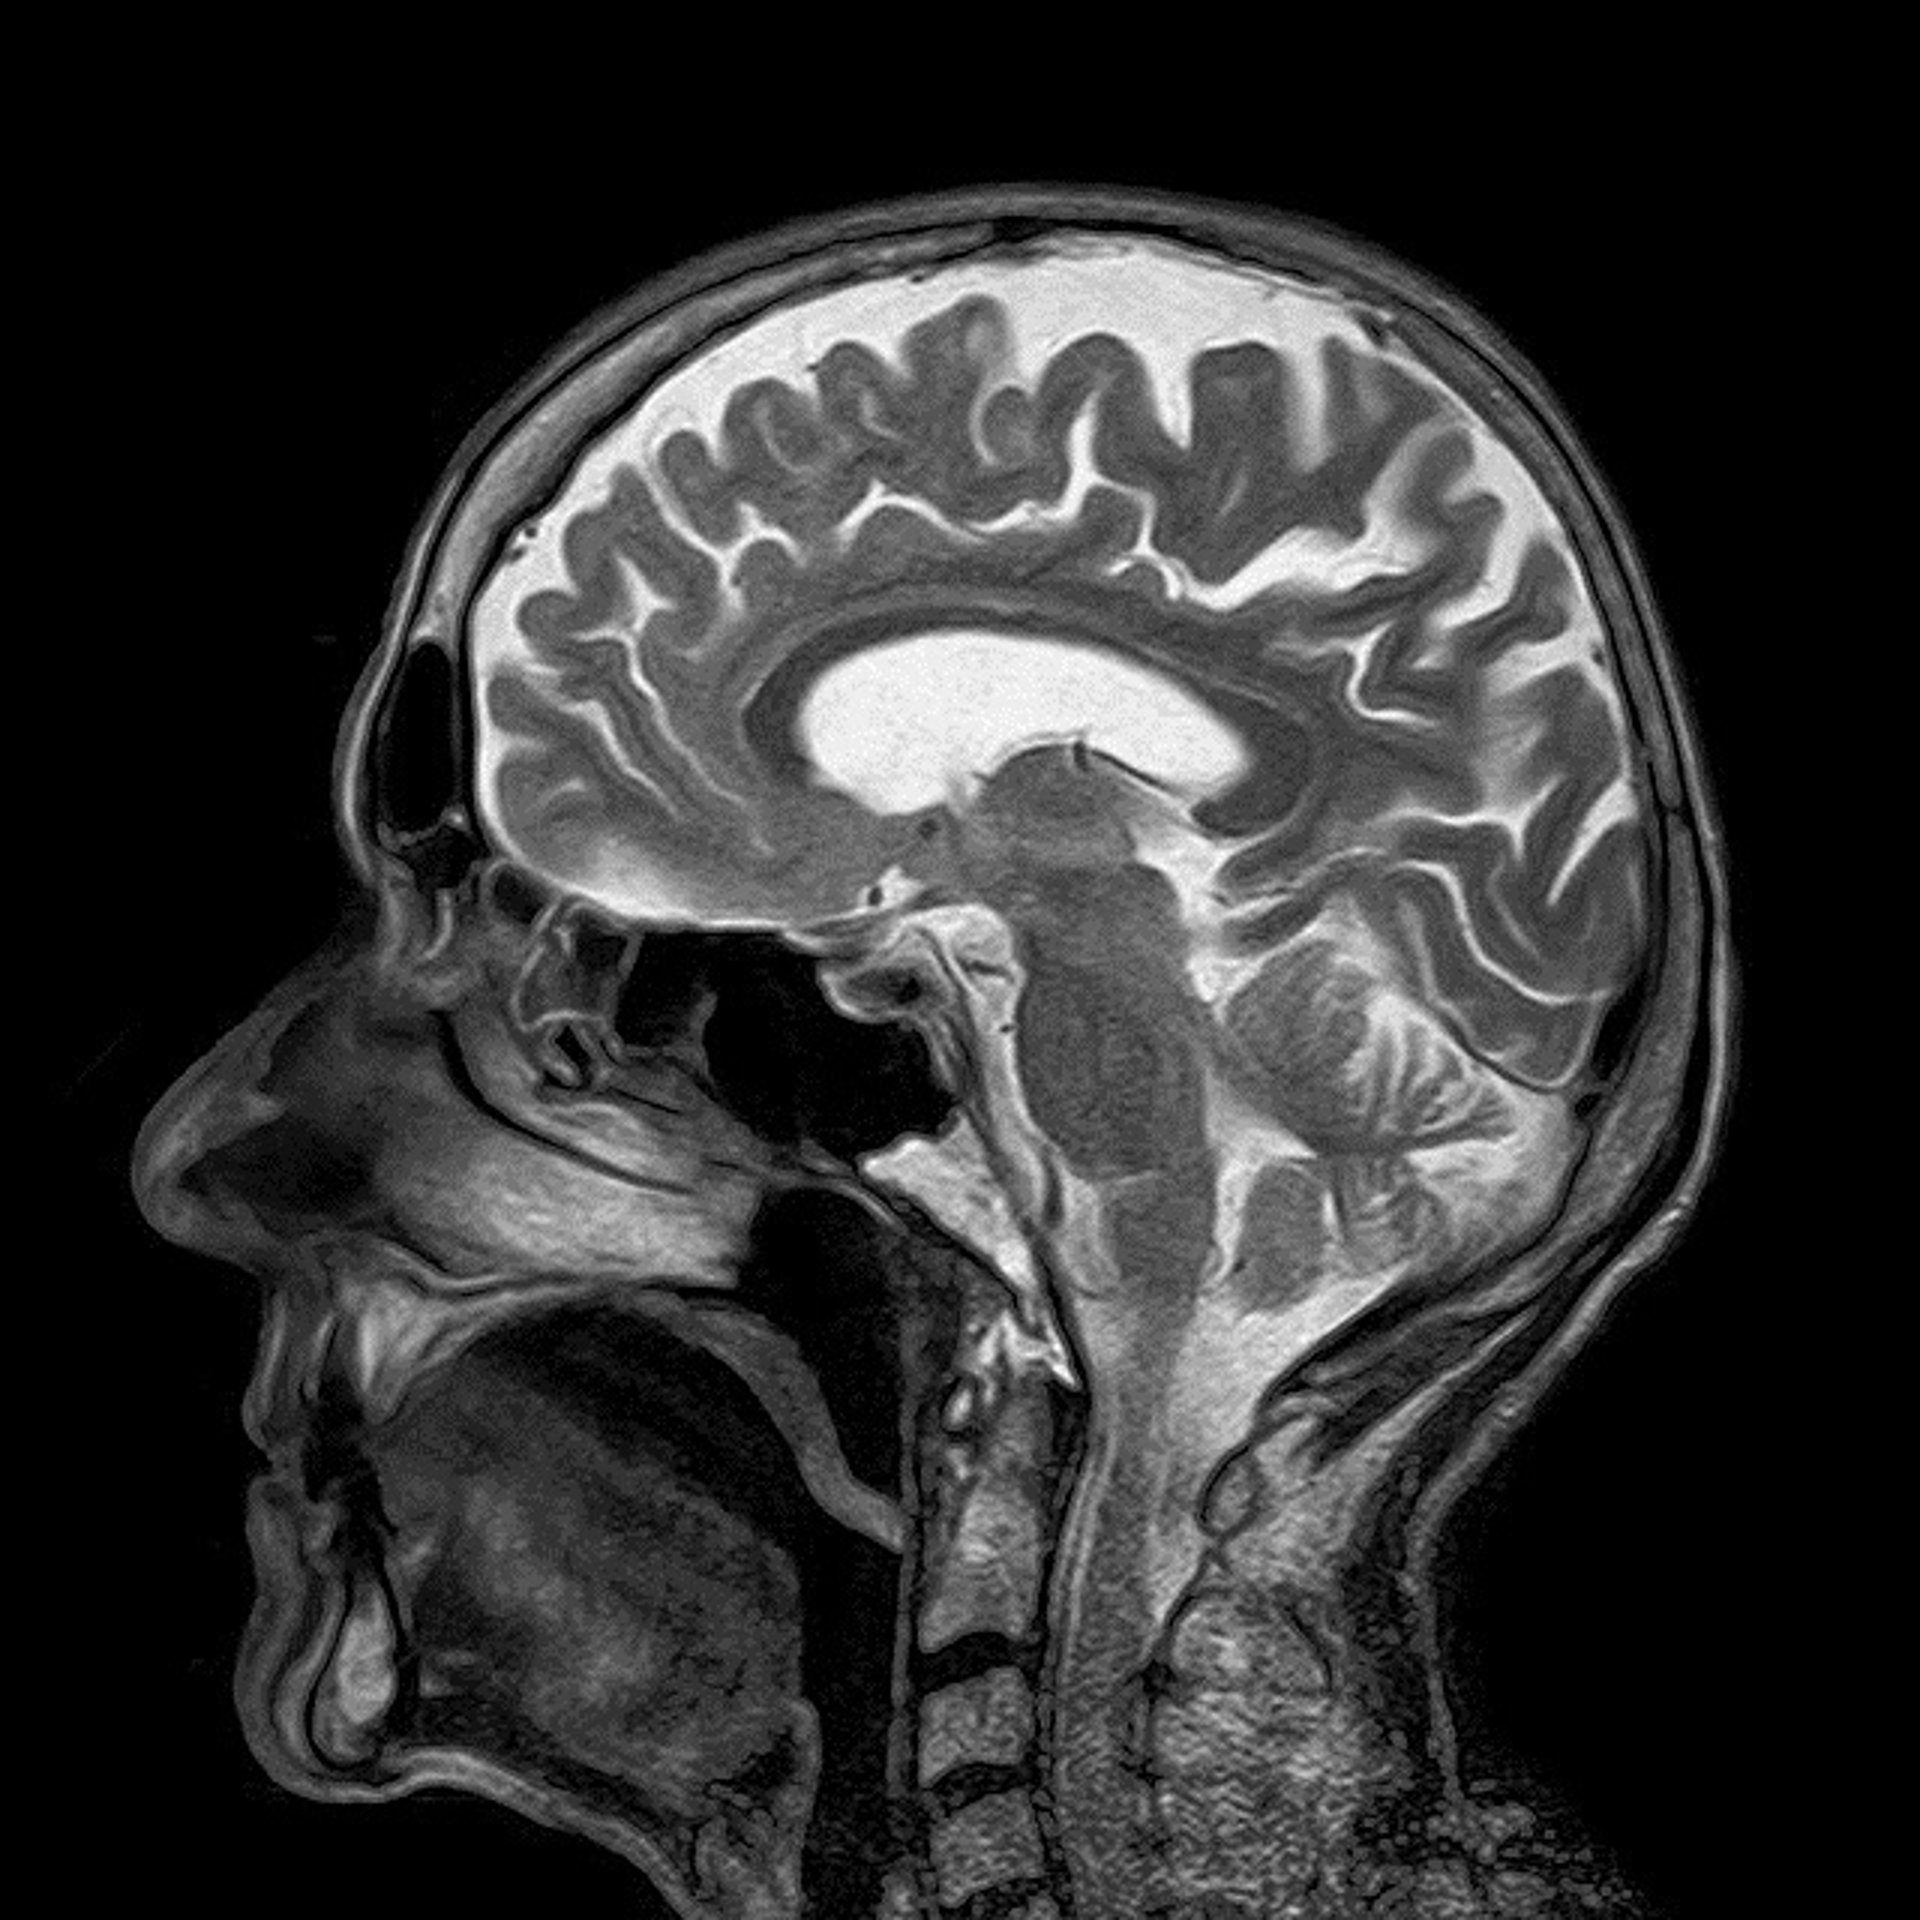

Cerebro

PIXABAY